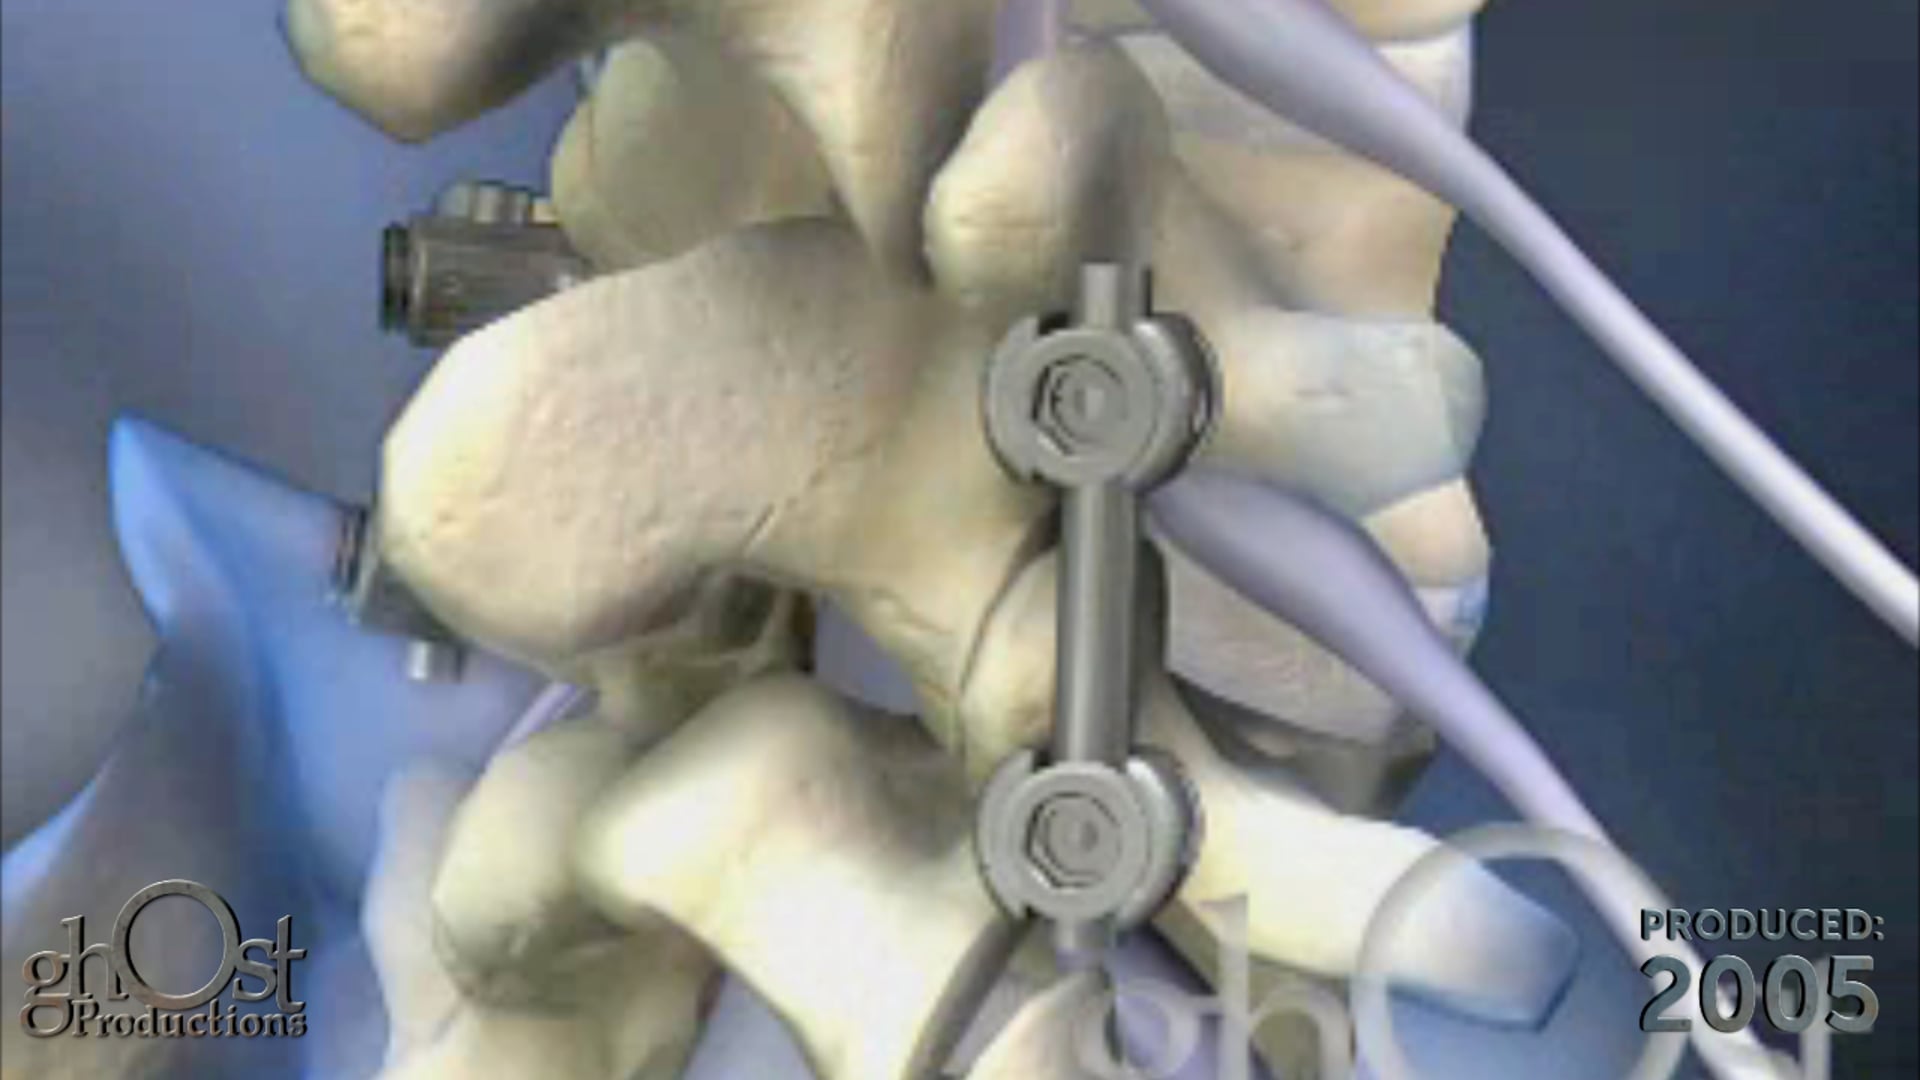

Expanding Orthopedics partners with Ghost Productions to create an animation showcasing their VCF posterior lumbar fixation system for spinal stabilization.

Expanding Orthopedics has collaborated with Ghost Productions to create an informative animation showcasing their VCF posterior lumbar fixation system. This innovative device is designed to stabilize spinal motion and promote interbody bone fusion in patients suffering from vertebral compression fractures. The animation demonstrates how the threaded interbody fusion cage is inserted into the lumbar disc space and used in conjunction with standard pedicle screws to provide optimal support and healing. This video is a valuable resource for medical professionals seeking to learn more about this cutting-edge technology in the field of orthopedics.

Expanding Orthopedics, Ghost Productions, VCF posterior lumbar fixation system, spinal motion stabilization, interbody bone fusion, vertebral compression fractures, threaded interbody fusion cage, lumbar disc space, pedicle screws, optimal support, healing, medical professionals, cutting-edge technology, orthopedics.